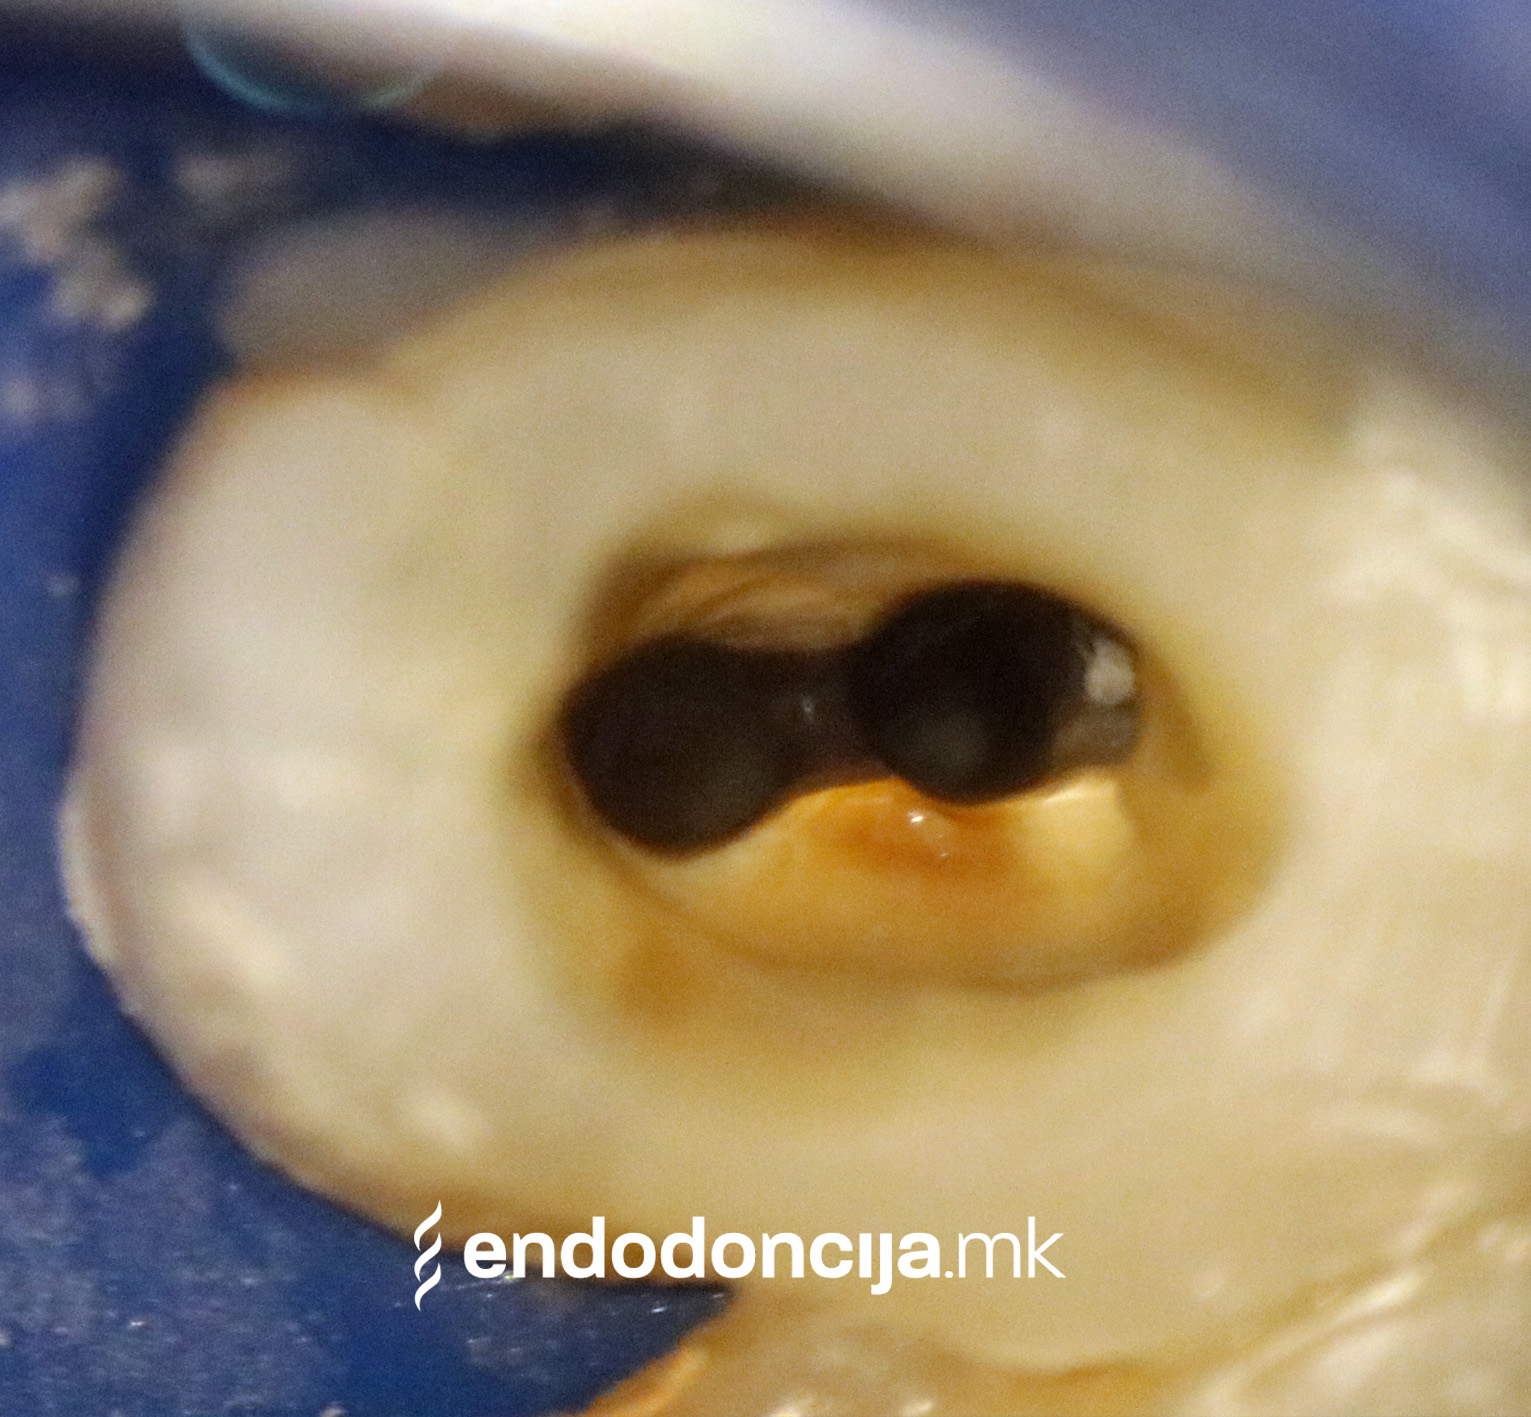

На специјализираниот оддел за ендодонција, нашите пациенти ги лекуваме на највисоко професионално и дијагностичко ниво. Опремени сме со најсовремени хируршки микроскопи, кои поддржуваат детален приказ и подготовка на коренот и нудат комплетно ново ниво на прецизност. Најновата ендодонтска опрема, инструментите и материјалите за полнење се во секојдневна употреба. На овој начин третманот станува пократок, дури и во комплицирани случаи, и се избегнува губење на забите.

Она што е импресивно е прецизноста на микроскопските третмани. Дури и кога каналите се потешко достапни, може да се лоцираат и исчистат така што релапсите се со помала веројатност. Спротивно на тоа, скриените канали често остануваат неоткриени во конвенционалниот третман на коренскиот канал и затоа не можат да се чистат. Бактериите можат да се размножуваат таму без пречки и да предизвикаат воспаленија. Ова често останува незабележано со години додека не се појави забоболка, а со тоа и компликации.

Употребата на микроскоп исто така овозможува детектирање пукнатини или фрактури што може да предизвикаат болка или воспаление.